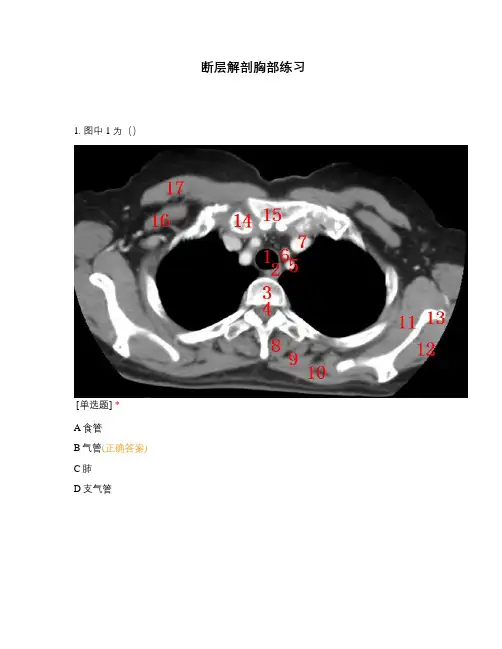

断层解剖胸部练习1. 图中1为()[单选题] *A食管B气管(正确答案)C肺D支气管[单选题] *A食管(正确答案) B气管C奇静脉D支气管[单选题] *A椎间盘B胸骨柄C椎体(正确答案) D脊髓[单选题] *A椎间盘B胸骨柄C椎体D脊髓(正确答案)[单选题] *A左锁骨下动脉(正确答案) B左颈总动脉C左头臂静脉D右锁骨下动脉[单选题] *A右颈总动脉B左颈总动脉(正确答案) C左头臂静脉D右锁骨下动脉[单选题] *A右头臂静脉B右颈总动脉C左头臂静脉(正确答案) D右锁骨下动脉[单选题] *A大菱形肌B竖脊肌(正确答案) C斜方肌D肩胛下肌[单选题] *A大菱形肌(正确答案) B竖脊肌C斜方肌D肩胛下肌[单选题] *A大菱形肌B竖脊肌C斜方肌(正确答案) D肩胛下肌[单选题] *A冈下肌B竖脊肌C斜方肌D肩胛下肌(正确答案)[单选题] *A冈下肌(正确答案) B竖脊肌C斜方肌D肩胛下肌[单选题] *A右髂骨B左髂骨C左肩胛骨(正确答案) D右肩胛骨[单选题] *A右锁骨(正确答案) B左锁骨C肋骨D胸骨柄[单选题] *A右锁骨B左锁骨C肋骨D胸骨柄(正确答案)[单选题] *A胸大肌B胸小肌(正确答案) C斜方肌D背阔肌[单选题] *A胸大肌(正确答案) B胸小肌C斜方肌D背阔肌[单选题] *A CT平扫B CT增强(正确答案) C肺窗D骨窗[单选题] *A胸骨柄(正确答案) B肋骨C锁骨D剑突[单选题] *A右头臂静脉B左头臂静脉(正确答案) C头臂干D左颈总动脉[单选题] *A右头臂静脉(正确答案) B左头臂静脉C头臂干D左颈总动脉[单选题] *A右头臂静脉B左头臂静脉C头臂干(正确答案) D左颈总动脉[单选题] *A右头臂静脉B左头臂静脉C头臂干D左颈总动脉(正确答案)[单选题] *A左锁骨下动脉(正确答案) B左头臂静脉C头臂干D左颈总动脉[单选题] *A食管B气管(正确答案) C肺D支气管[单选题] *A食管(正确答案) B气管C奇静脉D支气管[单选题] *A椎间盘B胸骨柄C椎体(正确答案) D脊髓[单选题] *A椎间盘B胸骨柄C椎体D脊髓(正确答案)[单选题] *A纵膈窗(正确答案) B 肺窗C骨窗D以上都不正确[单选题] *A胸骨(正确答案) B肋骨C锁骨D剑突[单选题] *A上腔静脉(正确答案) B下腔静脉C主动脉弓D肺动脉干[单选题] *A上腔静脉B下腔静脉C主动脉弓(正确答案) D肺动脉干[单选题] *A食管B气管(正确答案) C肺D支气管[单选题] *A食管(正确答案) B气管C奇静脉D支气管[单选题] *A椎间盘B胸骨柄C椎体(正确答案) D脊髓[单选题] *A椎间盘B胸骨柄C椎体D脊髓(正确答案)[单选题] *A大菱形肌B竖脊肌(正确答案) C斜方肌D肩胛下肌[单选题] *A右髂骨B左髂骨C左肩胛骨(正确答案) D右肩胛骨[单选题] *A冈下肌B竖脊肌C斜方肌D肩胛下肌(正确答案)[单选题] *A冈下肌(正确答案) B竖脊肌C斜方肌D肩胛下肌[单选题] *A大菱形肌(正确答案) B竖脊肌C斜方肌D肩胛下肌[单选题] *A大菱形肌B竖脊肌C斜方肌(正确答案) D肩胛下肌[单选题] *A胸大肌B胸小肌(正确答案) C斜方肌D背阔肌[单选题] *A胸大肌(正确答案) B胸小肌C斜方肌D背阔肌[单选题] *A上腔静脉B下腔静脉C升主动脉(正确答案) D主动脉弓[单选题] *A上腔静脉(正确答案) B下腔静脉C主动脉弓D肺动脉干[单选题] *A右肺动脉B左肺动脉(正确答案) C主动脉弓D肺动脉干[单选题] *A食管B气管C左主支气管(正确答案) D右主支气管[单选题] *A食管B气管C左主支气管D右主支气管(正确答案)[单选题] *A食管B气管C奇静脉(正确答案) D支气管。